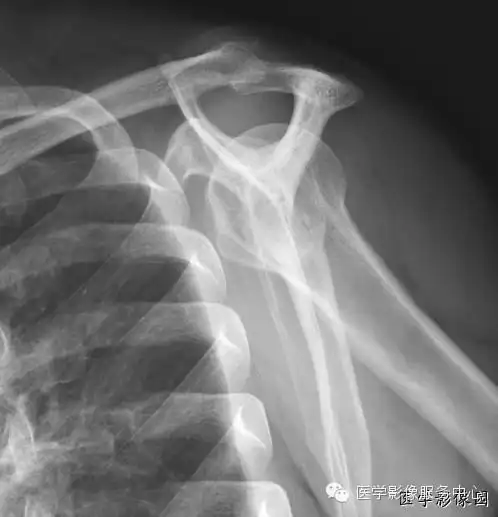

肩关节岗上肌出口位即y位